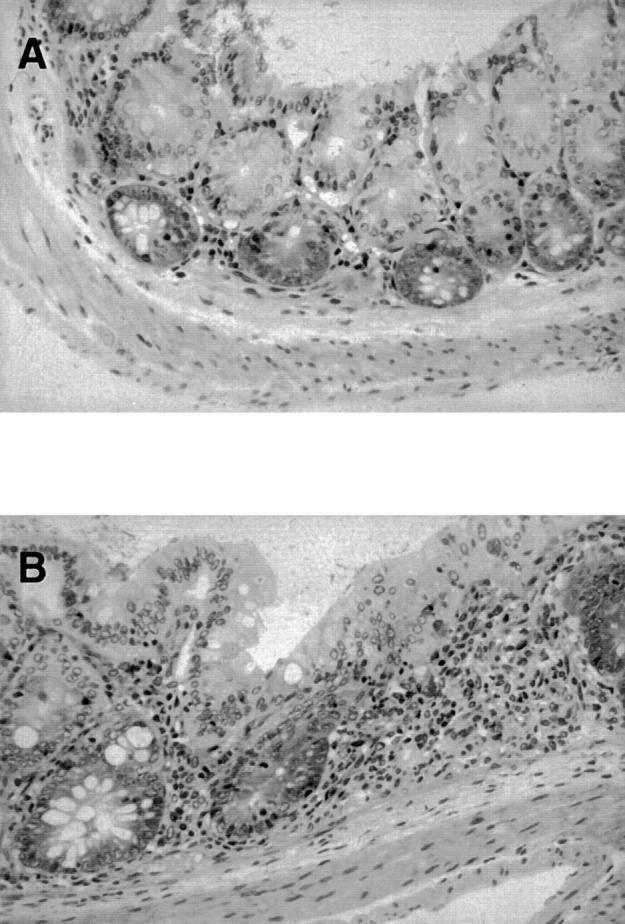

The orphan receptor CRF2-4 is a member of the class II cytokine receptor family (CRF2), which includes the interferon receptors, the interleukin (IL) 10 receptor, and tissue factor. CRFB4, the gene encoding CRF2-4, is located within a gene cluster on human chromosome 21 that comprises three interferon receptor subunits. To elucidate the role of CRF2-4, we disrupted the CRFB4 gene in mice by means of homologous recombination. Mice lacking CRF2-4 show no overt abnormalities, grow normally, and are fertile. CRF2-4 deficient cells are normally responsive to type I and type II interferons, but lack responsiveness to IL-10. By approximately 12 wk of age, the majority of mutant mice raised in a conventional facility developed a chronic colitis and splenomegaly. Thus, CRFB4 mutant mice recapitulate the phenotype of IL-10-deficient mice. These findings suggest that CRF2-4 is essential for IL-10-mediated effects and is a subunit of the IL-10 receptor.